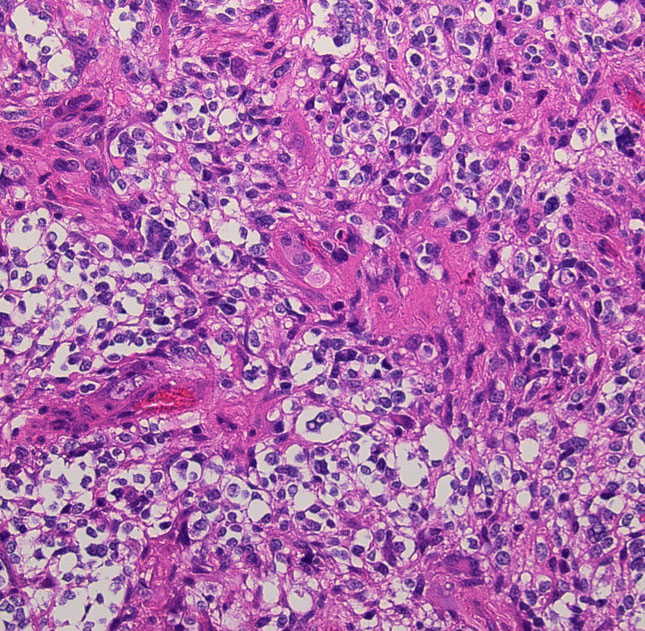

これは普通の病理組織診断です。これだけで膠芽腫という診断はつきます,

bizarre! 異様な細胞が混在しています。核多型が目立ち,多核巨細胞も混じる典型的な膠芽腫の像です。下の左の画像は血管内皮の肥厚 endovascular proliferationがあり,下の右のKi-67染色では核濃染像が多く核分裂能が高いことを示します。しかし,——